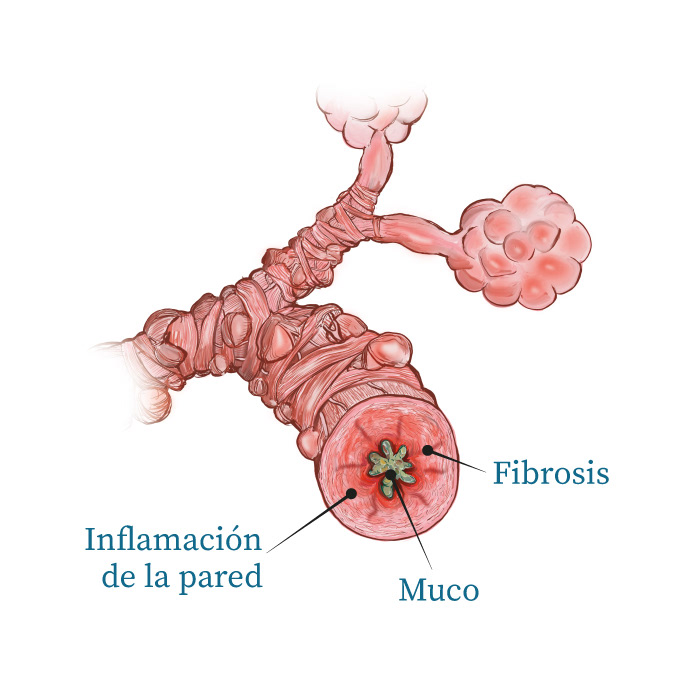

Proceso / Bronquiolitis